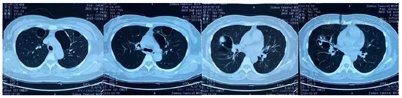

③胸部CT平扫+增强(2021年3月16日)右肺上叶有一巨大包块,病灶内可见分隔影,病灶周围可见钙化,增强后周围环形强化。右肺上叶及左肺上叶囊性病变内见不规则结节状实性密度影,呈新月征(图3)